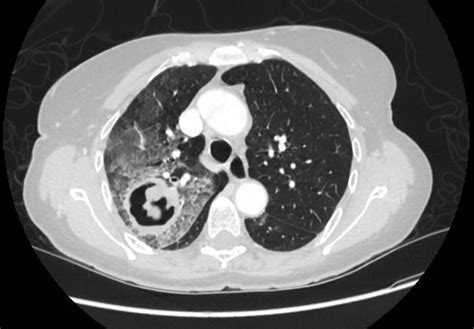

A cavitary lesion of lung is a significant radiological finding that requires careful medical evaluation. In clinical terms, a cavity is defined as a gas-filled space within a pulmonary consolidation, a mass, or a nodule. When a patient undergoes a chest X-ray or a computed tomography (CT) scan and receives this diagnosis, it often triggers immediate concern. However, understanding that these lesions can result from a wide spectrum of causes—ranging from common infections to serious malignancies—is crucial for both patients and healthcare providers to ensure accurate diagnosis and appropriate management.

At its core, a cavitary lesion of lung represents a localized area of the lung parenchyma that has been destroyed or excavated. This destruction often occurs when an area of diseased lung tissue undergoes necrosis—the death of cells—and the necrotic material is subsequently evacuated, usually through the bronchial tree. This leaves behind a hollow, air-filled void that appears distinctly on medical imaging.

Distinguishing Features on Imaging

Radiologists look for specific markers to help narrow down the diagnosis. The appearance of the cavity's wall, for instance, provides vital clues:

• Thick, Irregular Walls: These are more suggestive of malignancy (e.g., squamous cell carcinoma).

• Air-Fluid Levels: Highly indicative of a lung abscess, suggesting a collection of pus that has not yet been fully drained.